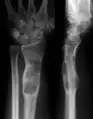

X-ray showing calcified enchondromas localized in finger a 37-year-old patient affected with Ollier disease

X-ray showing enchondromas localized in the humerus of a 37-year-old patient affected with Ollier disease

X-ray showing enchondromas localized in the lower part of the radius of a 37-year-old patient affected with Ollier disease